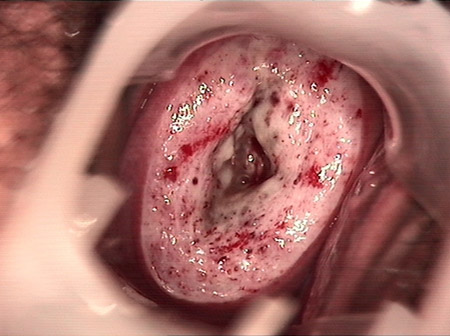

• CIN 2-3CIN 2-3

• CIN 2-3 碘著色后CIN 2-3 碘著色后